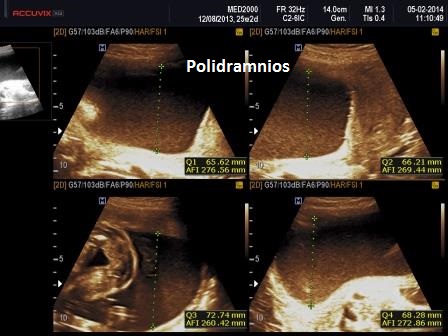

1. polidramnios (legato ai disturbi della deglutizione)